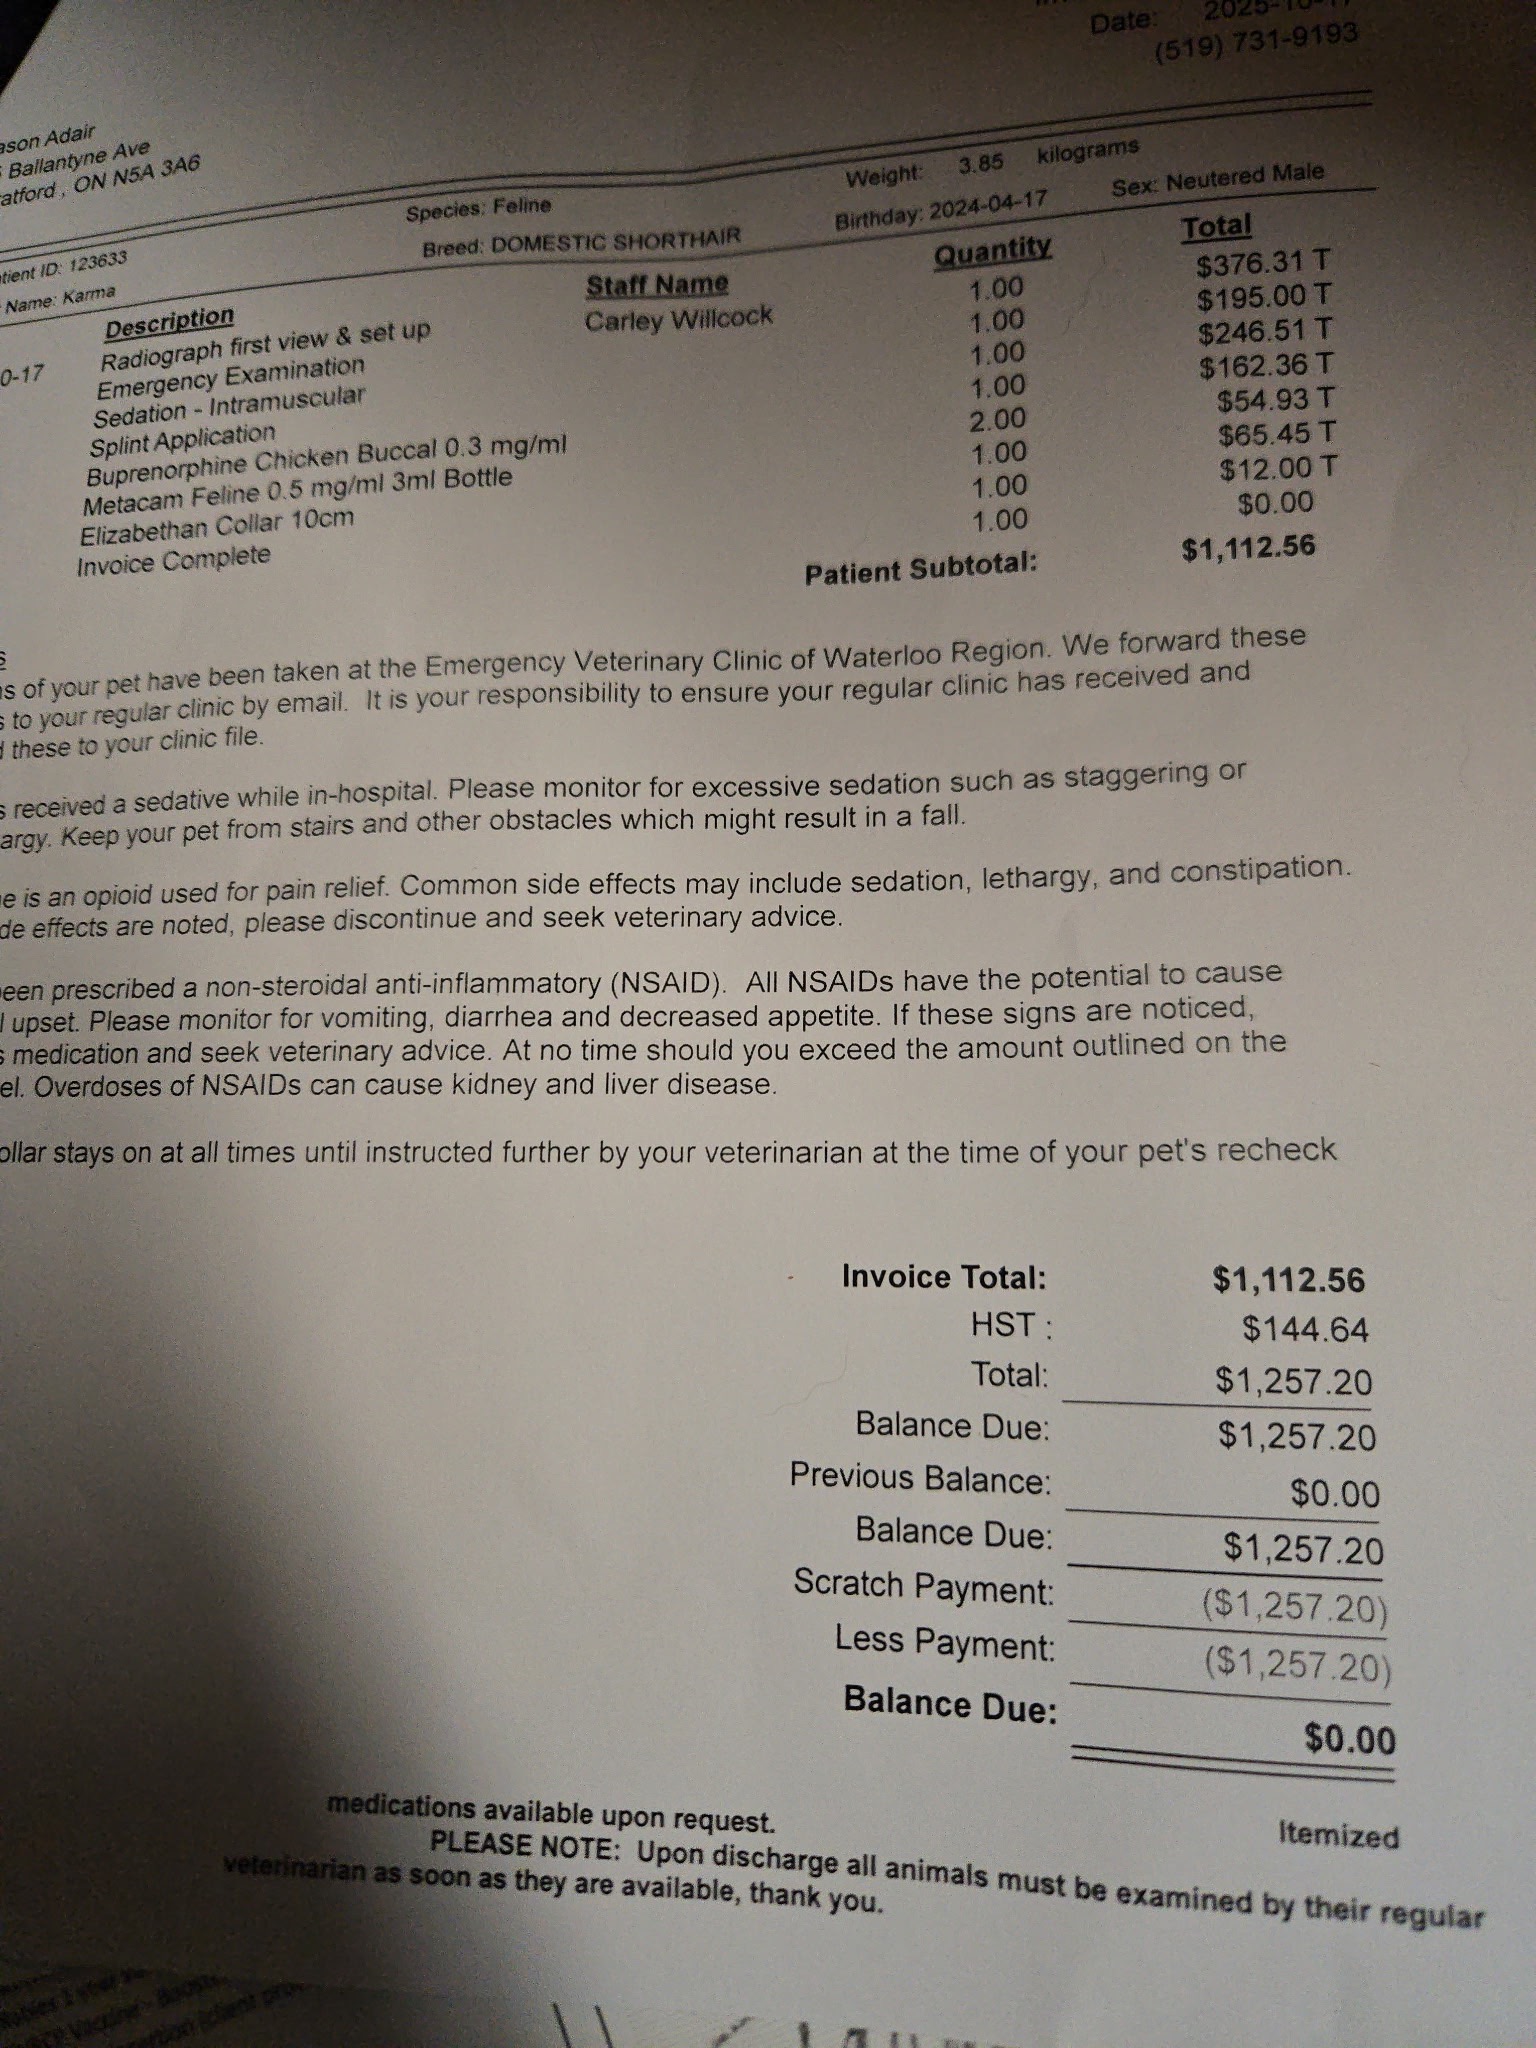

Hello, yesterday morning we discovered my sweet boy Karma was injured and after getting x rays we learned he has broken both of his lower leg bones and ankle. The options we were given was surgery for $7000 or amputation for $2000. We are working on finding somewhere that may be able to help at a lower cost but even so this is a very large unexpected expense. He is one of the sweetest cats and loved by everyone that knows him. Any donations or even a share would be greatly appreciated. We just want to get him help as soon as possible so he is no longer suffering. Examination fees, X-rays etc have already totalled over $1400. We are unfortunately likely opting for amputation to keep the costs lower.